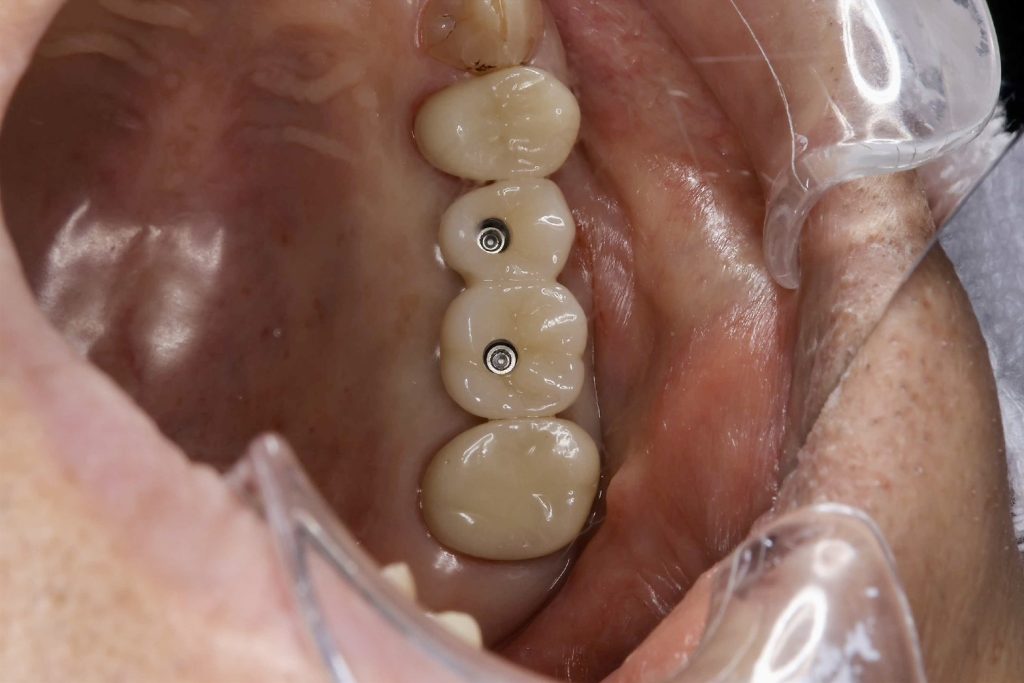

50代、男性、左上に違和感があることを主訴に来院され、インプラント治療を行いました。

| 治療内容 | 抜歯即時インプラント |

| 治療期間 | 10週間 |

| 治療費用 | ¥946,000(税込) |